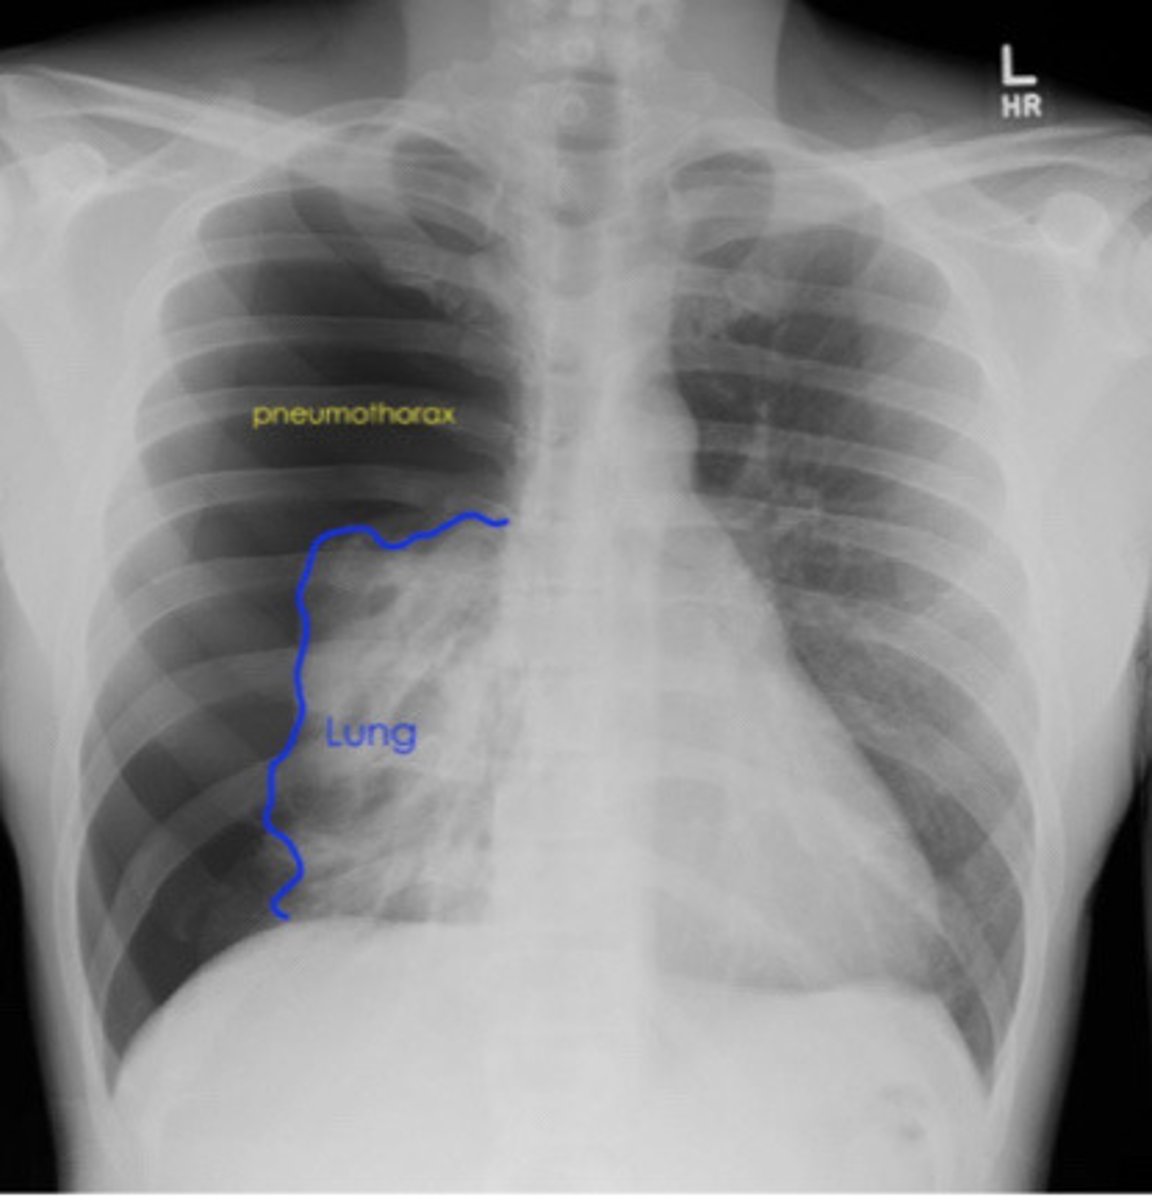

Types of pneumothorax

Iatrogenic: secondary to procedure

Primary spontaneous: healthy pts, no trauma

Secondary spontaneous: known lung dx

92

New cards

GS diagnostic testing for pneumothorax

Upright PA CXR

96

Visualization of visceral pleural line on CXR is indicative of

Pneumothorax

<p>Pneumothorax</p>